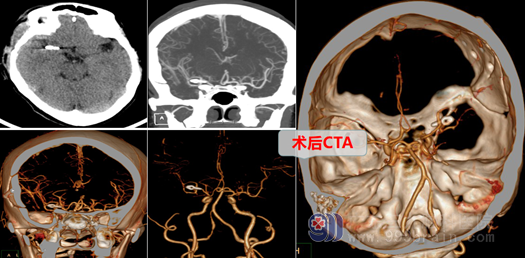

吕某转入后,经欧阳辉主任带领神经外十科团队讨论后,决定尽快给患者吕某采取外科直接开颅手术,行“右侧大脑中动脉M1段分叉处动脉瘤夹闭术”进行抢救、治疗,他们以“生命至上”的理念,迅速在全麻下切开头皮,翻开皮瓣。切开、剥离颞肌、骨膜,骨瓣开颅后,在显微镜下分开侧裂,仔细寻找大脑中动脉M1、分叉及其M2段等,在分叉处见到囊状动脉瘤,大小约2.6mm,瘤顶指向外侧,欧阳主任剑胆琴心,用一枚动脉瘤夹精准地直接夹闭了动脉瘤颈;检查中动脉上、下干均通畅,局部无活动性出血,脑组织及血管保护良好,脑搏动良好,手术过程顺利,达到手术目的。术后返回监护室,患者返病房后神志清醒,四肢肌力肌张力正常。吕某脱离了危险,幸运地逃过一劫。